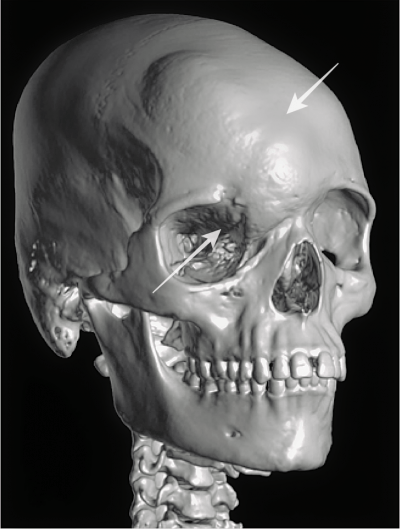

Fractura de pómulo

La fractura del hueso malar provoca el hundimiento del pómulo, alteración de la posición del ojo o distopia ocular, visión doble y disminución de sensibilidad en la mejilla y los dientes.

Fractura ocular

Fractura órbita